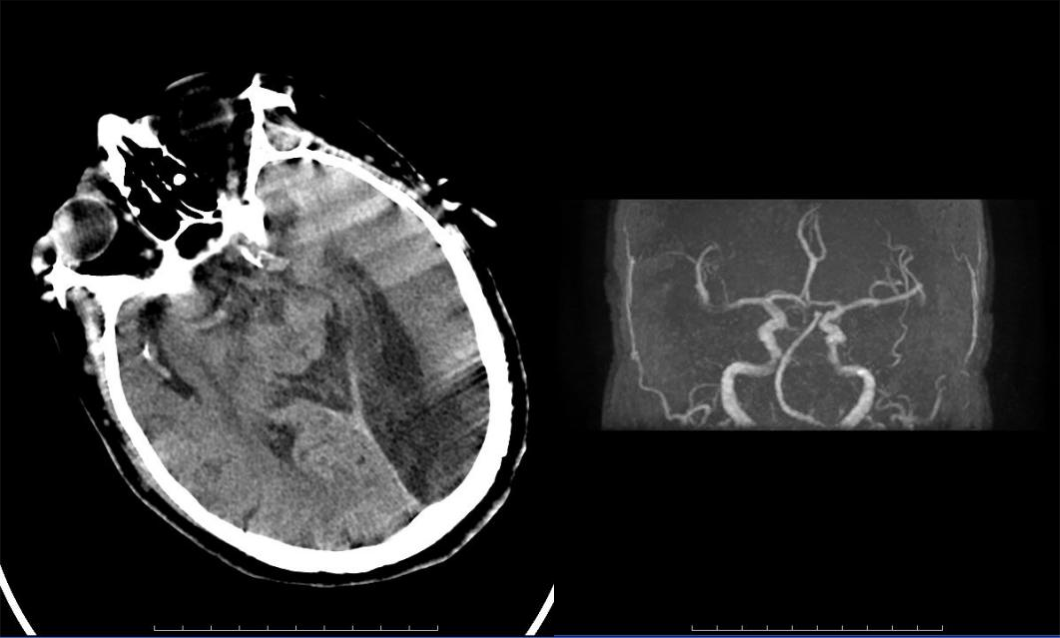

病历三:患者,78岁女性,因左侧肢体无力、右上肢抽搐、言语不清2小时伴意识模糊入院。

介入团队采取上述同样技术取出条块状暗红色血栓,质韧,考虑为心源性栓塞。

大脑中动脉M1段分叉部以远闭塞,大脑中动脉上干开通,取出血栓。

目前患者病情平稳,仍在治疗中。